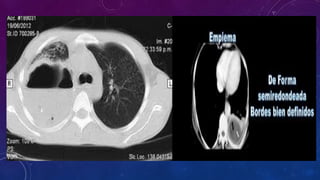

EMPIEMA

• Acumulación de pus en la cavidad

pleural, este puede ocupar parte de la

misma o toda ella. Empiema es el fluido

inflamatorio y la fibrina dentro del

espacio pleural, es el resultado de una

infección dentro de la cavidad pleural

que evoluciona de líquido acuoso a una

colección purulenta dentro del espacio

pleural.

DIAGNOSTICO